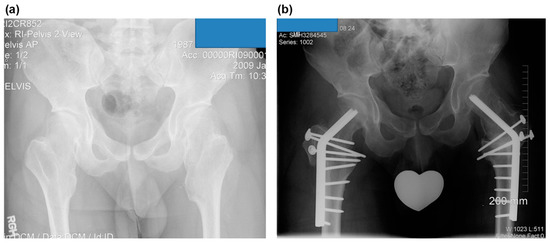

Figure 4.

The case of a 22-year-old man with symptomatic bilateral femoroacetabular impingement in MHE (case no. 6). (a) A preoperative anteroposterior radiograph of the hip shows a large bump at the medial side of the femoral neck and severe coxa valga. (b) Postoperative anteroposterior radiograph of the hip. Valgus intertrochanteric osteotomies were performed on both hips using blade plates, and the trochanteric osteotomy sites were fixed with 3.5 mm cortical screws.

All ten hips underwent surgery to excise osteochondromas using safe surgical hip dislocation [21] by the senior author (DP). One female and two male patients had staged bilateral surgeries. Varus intertrochanteric osteotomy was performed when the neck–shaft angle was more than 150° (Figure 4a,b). After surgery, follow-up was performed at 4-week intervals until a bony union was established, and thereafter, observations were made at intervals of 6 months to 1 year. All of the patients were followed with serial radiographs for a mean follow-up of 49 (range, 12–97) months.

All the additional correctional osteotomies were performed during the index surgery. Varus intertrochanteric osteotomy was done in five hips. Valgus intertrochanteric and distal femoral varus osteotomies were performed in one case (Langer–Giedion syndrome). However, no pelvic osteotomy was done.